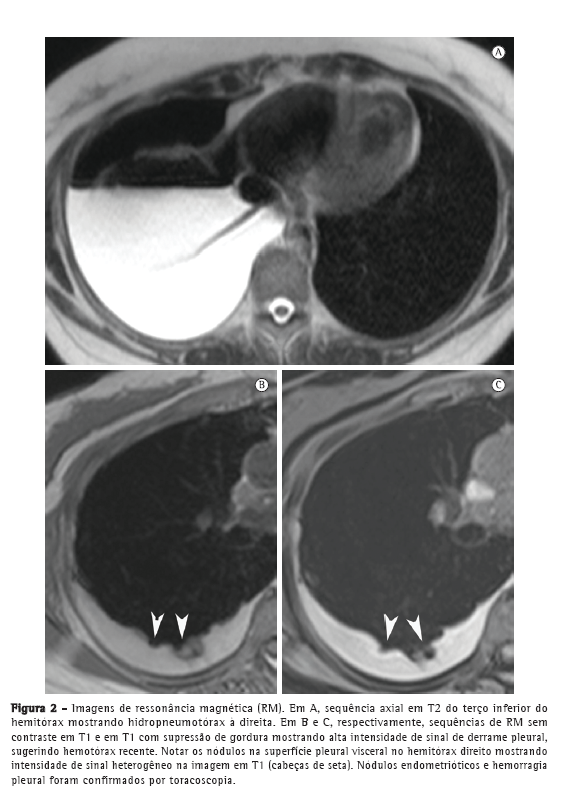

A paciente permaneceu assintomática por 4 anos. Aproximadamente seis meses antes do presente relato, a paciente apresentava dispneia cíclica, tosse seca e dor pélvica leve apesar do uso de contraceptivos orais. Uma radiografia e uma TC de tórax revelaram leve hidropneumotórax à direita. O parênquima pulmonar estava normal. Na RM de tórax em sequência T1 e T2, com e sem supressão de gordura, foi observado hidropneumotórax direito, e na RM em sequência T1 e supressão de gordura foram observadas lesões nodulares hiperintensas na pleura; algumas dessas lesões apresentavam difusão restrita (Figura 1), que é sugestiva de endometriomas.

Nos últimos anos, a RM de tórax progrediu muito. Devido a melhorias na velocidade e na qualidade das imagens, a RM está pronta para ser usada na rotina clínica.(7-9) Nos dois casos aqui apresentados, a RM de tórax revelou hidropneumotórax e nódulos arredondados bem definidos na superfície pleural do hemitórax direito. No Caso 1, o derrame pleural apresentou intensidade de sinal intermediária em T1, sugerindo alto conteúdo proteico, provavelmente relacionado a produtos da hemorragia. No Caso 2, o derrame pleural apresentou alta intensidade de sinal, sugerindo hemotórax recente. Os nódulos pleurais observados no Caso 1 mostraram homogeneidade na alta intensidade de sinal em imagens em T1 com supressão de gordura e difusão restrita em imagem ponderada em difusão (IPD). No Caso 2, os nódulos mostraram heterogeneidade na intensidade de sinal nas imagens em T1 e T2, sem restrição de difusão. De forma semelhante à endometriose pélvica,(1,10) os nódulos pleurais da endometriose torácica podem mostrar diferentes intensidades de sinal em imagens em T1 e T2, assim como na variação de restrição de difusão, dependendo da idade da lesão.